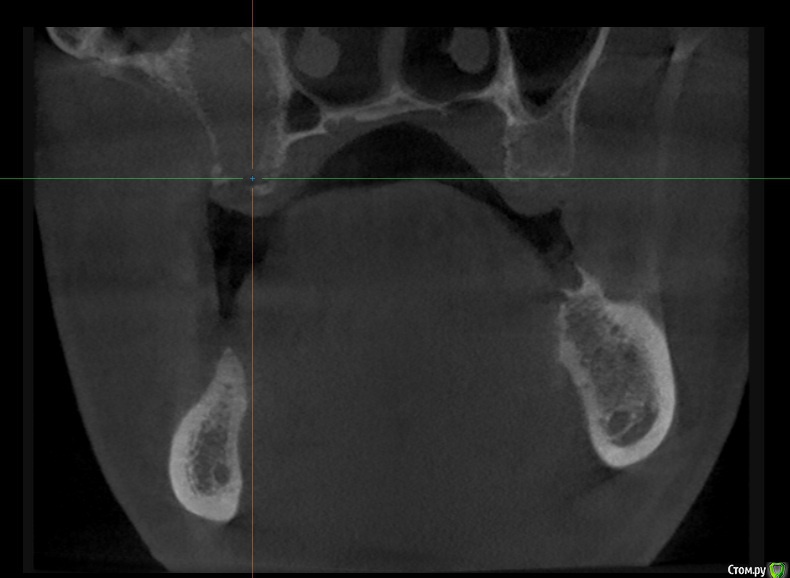

alboard Опубликовано 9 марта, 2017 Поделиться Опубликовано 9 марта, 2017 В области 16,17,18 дно отсутствует. Какая здесь может быть тактика? Ссылка на комментарий

Dok22 Опубликовано 9 марта, 2017 Поделиться Опубликовано 9 марта, 2017 В пазухе какое то образование. 1 Ссылка на комментарий

mr.Fog Опубликовано 9 марта, 2017 Поделиться Опубликовано 9 марта, 2017 Скорее всего это кальцифицированные останки радикулярной кисты. Ссылка на комментарий

Oscar Опубликовано 9 марта, 2017 Поделиться Опубликовано 9 марта, 2017 давно зубы удалены? Похоже на ретенционную кисту пазухи... Можно попробовать отслоить шнайдер снизу, если перфорация выход только "парашют"... Ссылка на комментарий

drpetrovich Опубликовано 13 марта, 2017 Поделиться Опубликовано 13 марта, 2017 Действительно по томограмме больше похоже на резидуальную кисту, т.е. при зондировании проваливаешься не в пазуху, а в полость кисты. Отделяемое было кстати? Вопрос про давность удаления актуален. Ссылка на комментарий